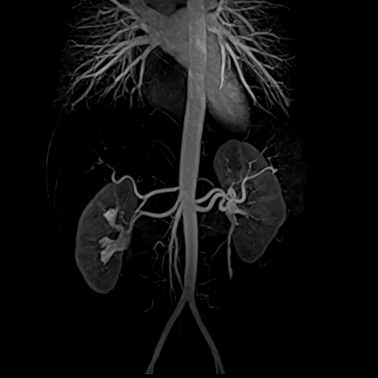

MRT der Gefäße (MR-Angiografie)

Dieses moderne bildgebende Verfahren ermöglicht umfassende und diagnostisch wichtige Aussagen über die arteriellen Gefäße. Untersucht werden vor allem die Becken-Bein-Gefäße, die Bauchgefäße und die Gefäße im Hals- und Kopfbereich. Nach Injektion eines nicht-jodhaltigen Kontrastmittels kann dessen Weg durch die jetzt stark kontrastierten Adern verfolgt und zwei- und dreidimensional dargestellt werden. Dank moderner MRT-Spulentechniken können auch lange Gefäße mit einer einzigen Aufnahme erfasst werden.

Nierenaterien